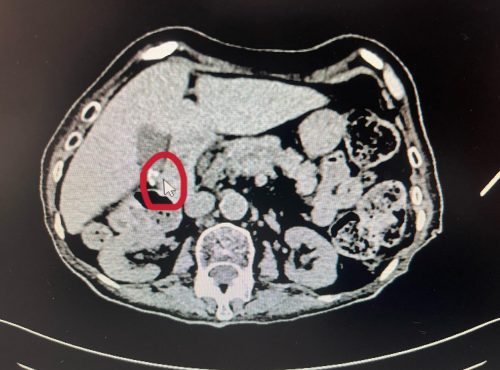

(南华大学附属长沙中心医院)肝胆胰脾疝外科就诊。完善相关检查后,医生发现其有胆囊结石、脑梗死、房颤、心脏瓣膜病、二尖瓣脱垂并关闭不全、三尖瓣关闭不全、心力衰竭、2型糖尿病、慢性胃炎、陈旧性胸椎骨折、肾结石、肺部感染、肺动脉高压、中度贫血等多种疾病。进一步完善CT检查后提示胆囊结石,胆囊炎,且经保守治疗效果不明显、炎症加重、腹痛加剧,如继续保守治疗,不排除胆囊穿孔的风险。老人有手术指征,但是家属考虑其高龄、手术风险大,决定先保守治疗。